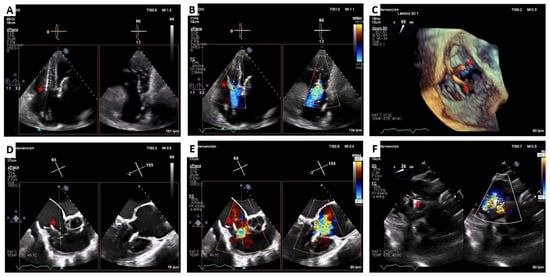

2. Cardiovalve Cases

4.2. Cardiovalve